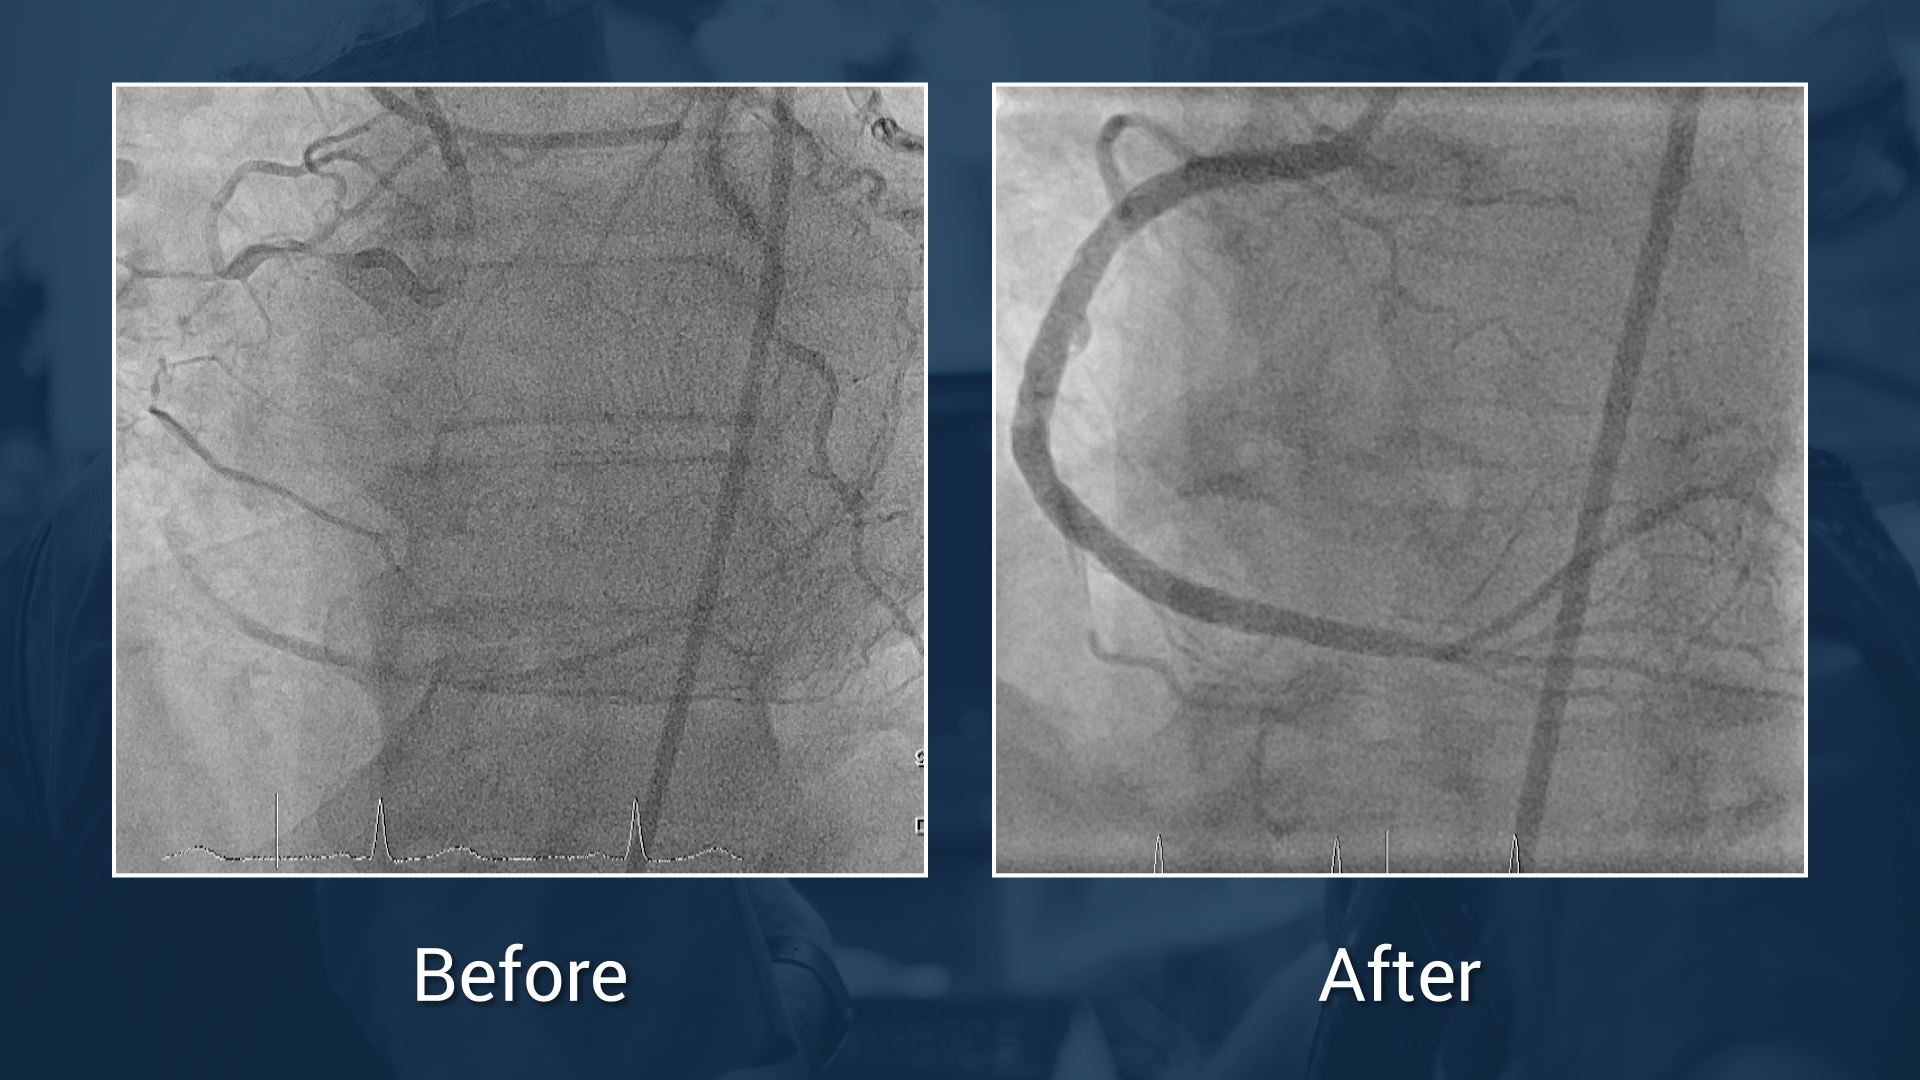

A long mid calcified RCA CTO with ambiguous proximal cap

Live case performed by Dr Avran & Dr Carlino

Triple vessel disease treated with FFR guidance

Downgrading from triple vessel disease to single vessel disease